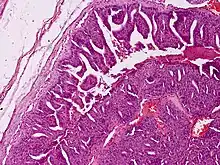

Histologically, the tumor exhibits a mixed tubuloalveolar and papillary pattern, focal squamous metaplasia, fibrocollagenous stroma, and a grenz zone.[5] In situ hybridization for HPV42 DNA may help in differentiating this cancer from related tumors.[6]